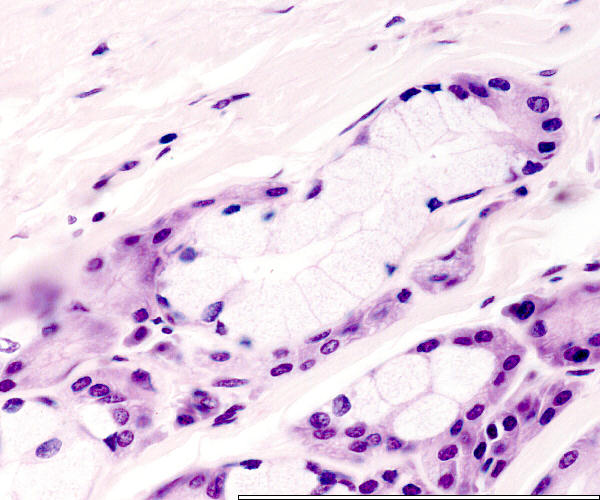

Faringeale buis

Pharyngeal tube